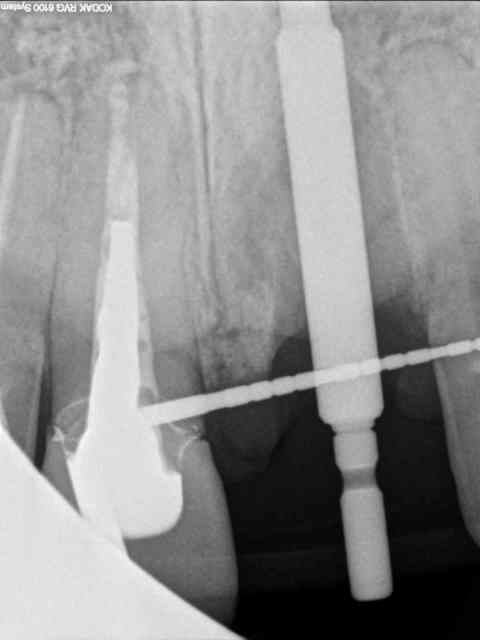

voici encore un autre cas avec du PX encore tout chaud de ce matin...

homme 35 ans veut faire recoller sa couronne 21.

le tenon est tordu, je refais une provisoire mais à la radio je lui dis que j'ai un doute quant à la survie de la dent parce qu'il y a une image pas très nette en mesial de la racine.

je l'envoi faire quelques coupes tomo (vivement que j'ai cone beam! )

le resultat est édifiant et sans appel; la racine est à extraire!

donc je m'y mets ce matin...

1 radio départ

2

OUPS !!

2-3-4 cas initiale avec provisoire

5 extraction avec periotome

6-7 l'objet du délit...

8 forage

9 jauge de profondeur

10 l'AXIOM PX

(diamètre 4; dans le cas précédent c'était un diamètre 3.4 on voit qu'ici il y a une réduction du diamètre du col de l'implant contrairement au 3.4 pour eviter de fragiliser l'implant)